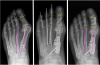

Theoretically, the surgeon would determine the location of where to perform the Akin procedure by identifying where the level of deformity is located within the proximal phalanx. Accomplish this by drawing a line bisecting the medullary shaft and compare that to a line that is perpendicular to the joint line of the articular side of the phalanx. The three options are: proximal, midshaft or distal. In the rare exception of a severe intrinsic deformity of the hallux at the distal or proximal side, it is my experience that a midshaft oblique osteotomy that extends into a metaphysis is the best method of correction. In most cases, the osteotomy is an adjunct to the bunion correction so theoretically, extreme degrees of deformity correction are not necessary and center of rotation of angulation (CORA) corrections of such a small bone are unnecessary in clinical practice. Most commonly, surgeons will perform wedge osteotomies of the proximal phalanx of the hallux with a lateral hinge. The benefits of the hinge are to act a single point of fixation when one combines this with another fixation source (i.e., screw, wire, staple). Through and through osteotomies can be beneficial to “dial” in the correction when the surgeon performs these in the transverse plane. Intraoperative fluoroscopy is extremely helpful to assess that the first MPJ and the hallux interphalangeal joints are parallel.